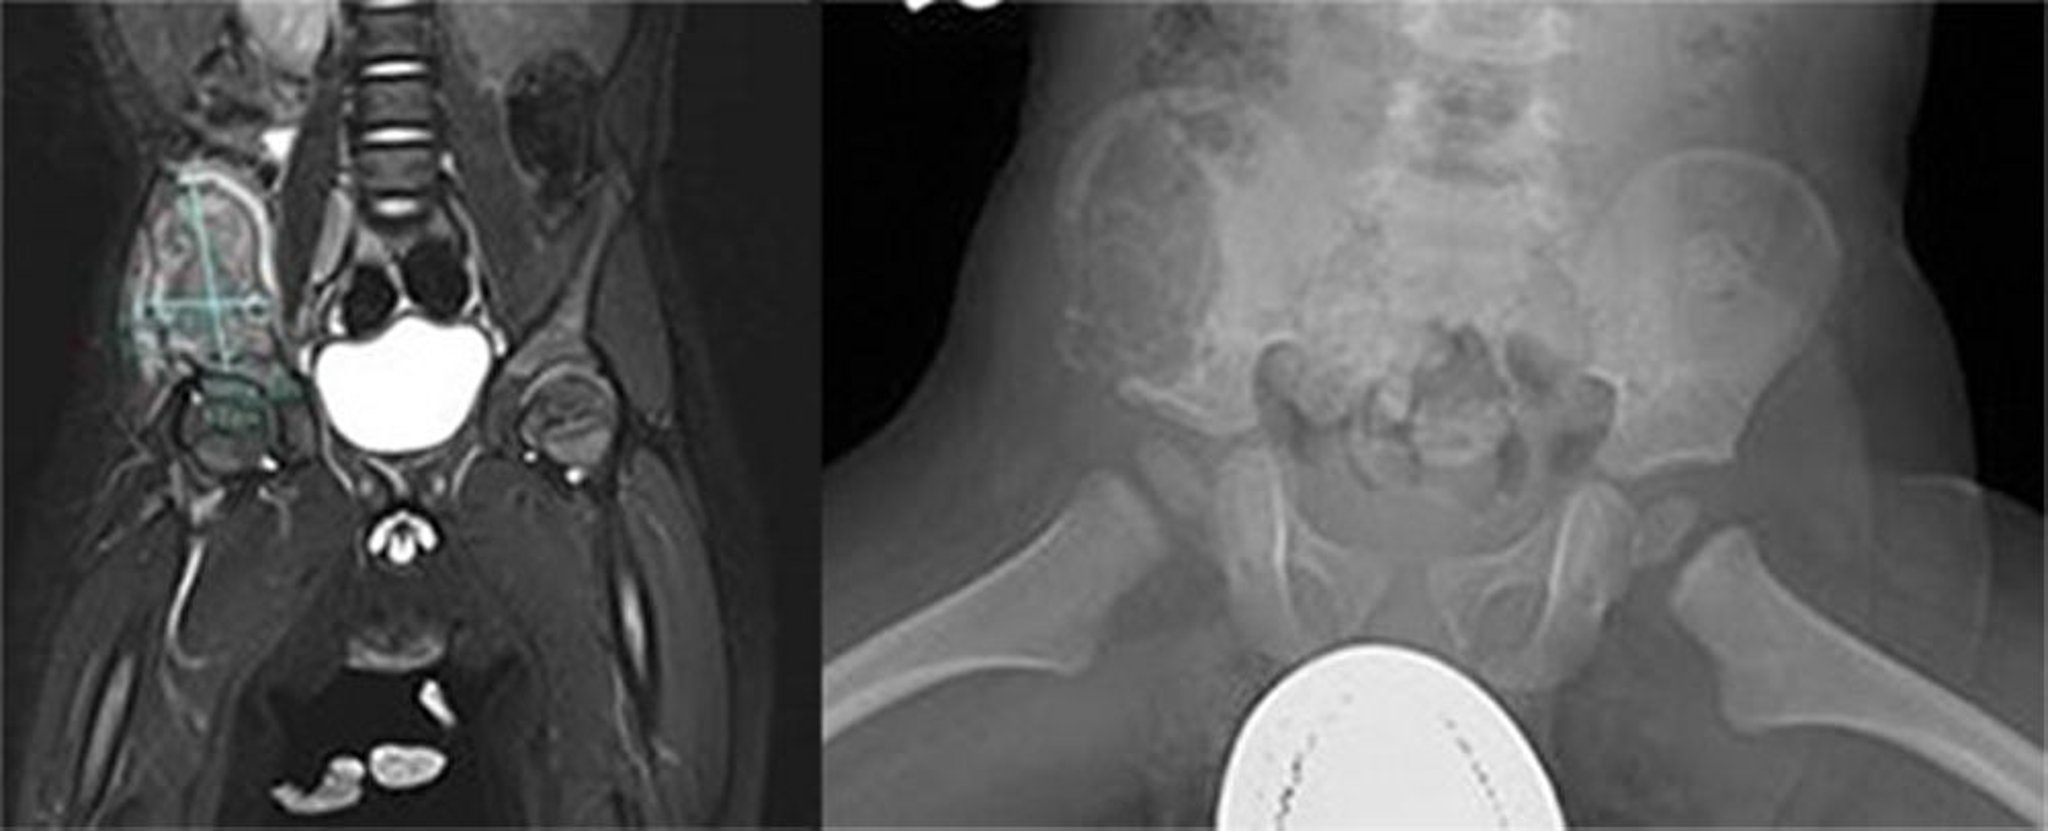

Histiocytose à cellules de Langerhans (os pelvien)

Cette image montre une grande lésion agressive de l'aile iliaque droite. Une IRM a révélé que la masse était hétérogène en T2 et à faible signal T1 avec augmentation hétérogène de la masse et de la musculature environnante avec déviation médiale du muscle psoas droit, suggérant une lésion osseuse agressive (gauche). Une grande lésion lytique au niveau de l'aile antérieure et latérale de l'iléon s'étendant en avant et en dessous de l'ischion était visible sur la radiographie (droite). Il existe une expansion du cortex et des irrégularités corticales. La biopsie a été diagnostique pour l'histiocytose à cellules de Langerhans.

Images courtesy of Carolyn Fein Levy, MD, and Jeffrey M. Lipton, MD, PhD.